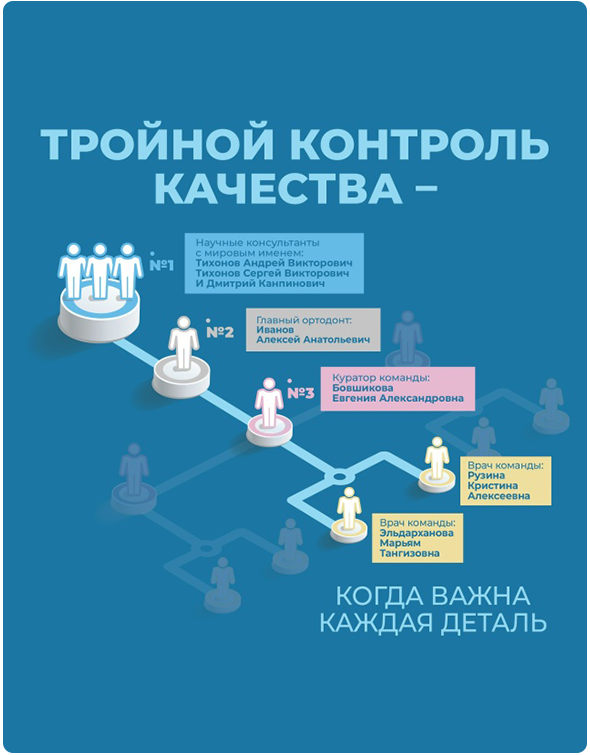

Выбор методики – задача специалиста-ортодонта. Опытные врачи клиник «Полный порядок» подбирают ортодонтическую конструкцию с учетом клинической ситуации пациента, его возраста, бюджета и т.д. В некоторых случаях аппараты даже комбинируют.